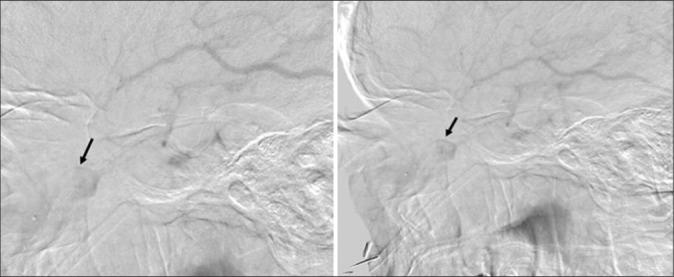

We report a case of a 74-year-old male with progressively painful unilateral proptosis. Imaging revealed the presence of an orbital mass compatible with a thrombosed orbital varix of the inferior ophthalmic vein in the left inferior intraconal space. The patient was medically managed. On a follow-up outpatient clinic visit, he demonstrated remarkable clinical recovery and denied experiencing any symptoms. Follow-up computed tomography scan showed a stable mass with decreased proptosis in the left orbit consistent with the previously diagnosed orbital varix. One-year follow-up orbital magnetic resonance imaging without contrast showed slight increase in the intraconal mass.